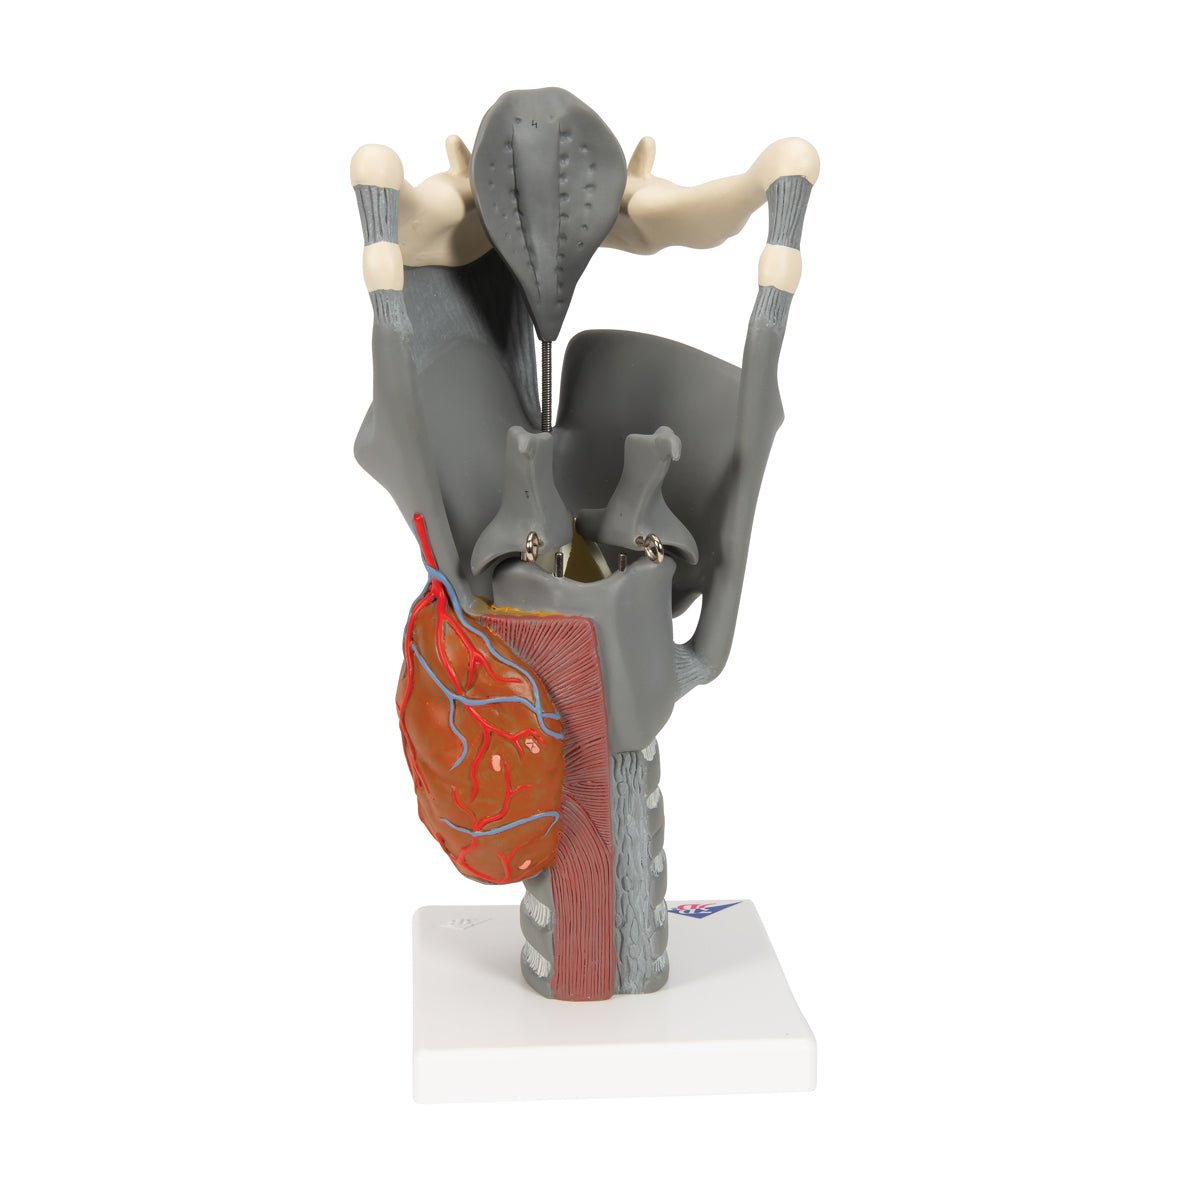

Anatomical models

Selling anatomical models is the mainstay of eAnatomi, although we also spend a lot of resources developing our own anatomical materials such as posters. Anatomical models are used for various purposes and can show both defined tissues, organs and organ systems. Are you looking for a simple model of bone tissue or perhaps an advanced torso model based on MRI technology, you can find it all at eanatomi.com.